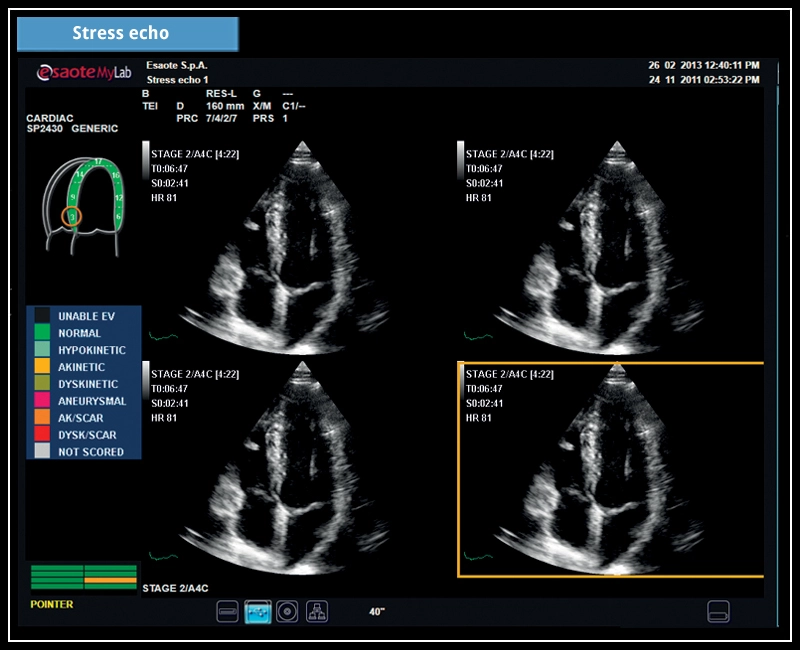

MyLab™X7 - Stress echo

MyLab™X7 - Stress echo